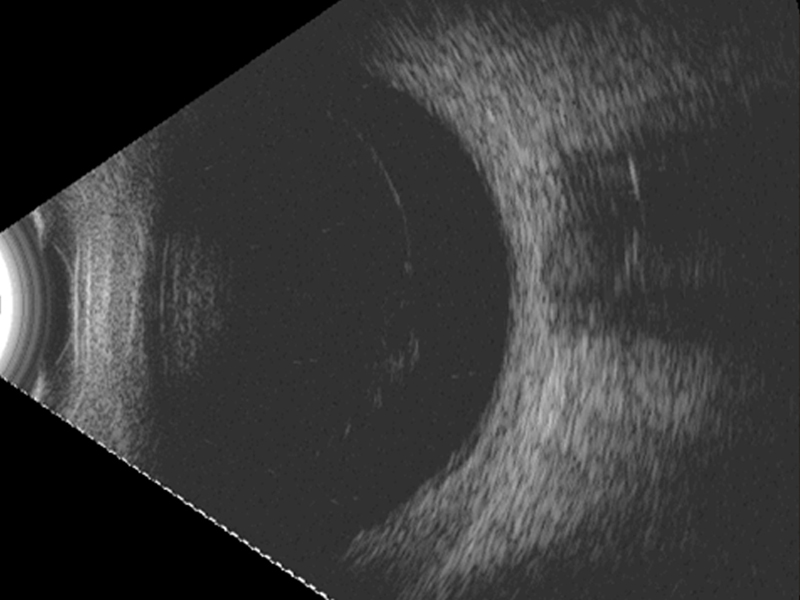

En modo B se aprecia una estructura de superficie regular, con alta reflectancia en su margen anterior y sombra acústica posterior (

Figura 8). Es habitual la presencia de membranas vítreas o de bridas que se insertan en la lente.

Figura 8. Cristalino en el polo posterior. Cara anterior lisa y de alta reflectancia, con importante sombra acústica por su alta densidad.